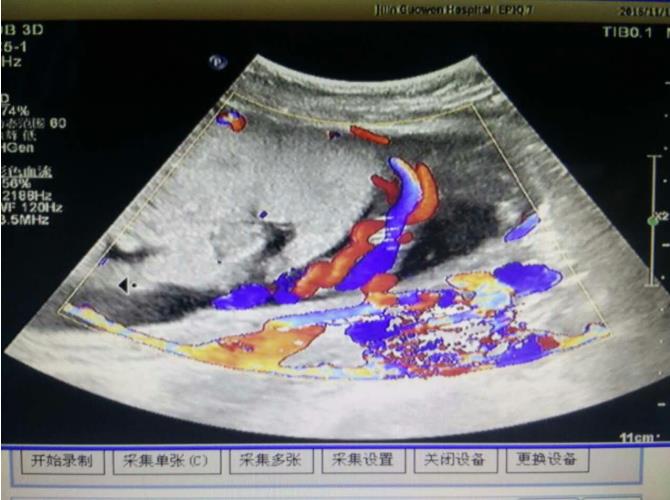

為該患常規(guī)檢查臍帶入口時(shí)發(fā)現(xiàn)臍帶入口位于胎盤下緣邊緣,胎兒超聲檢查無陽性發(fā)現(xiàn)。常規(guī)掃查右卵巢時(shí),發(fā)現(xiàn)右卵巢旁可見腎臟回聲(正常情況下,右卵巢旁是不會(huì)掃查到腎臟回聲的),大小、形態(tài)如常,CDFI:腎內(nèi)血流灌注尚可,故囑患者左側(cè)臥位,顯示孕婦右腎位置、大小及形態(tài)正常,囑孕婦右側(cè)臥位,發(fā)現(xiàn)脾臟下方無腎臟回聲,故考慮該患左腎游走腎。該患于2016年12月2日復(fù)查,結(jié)果如前。